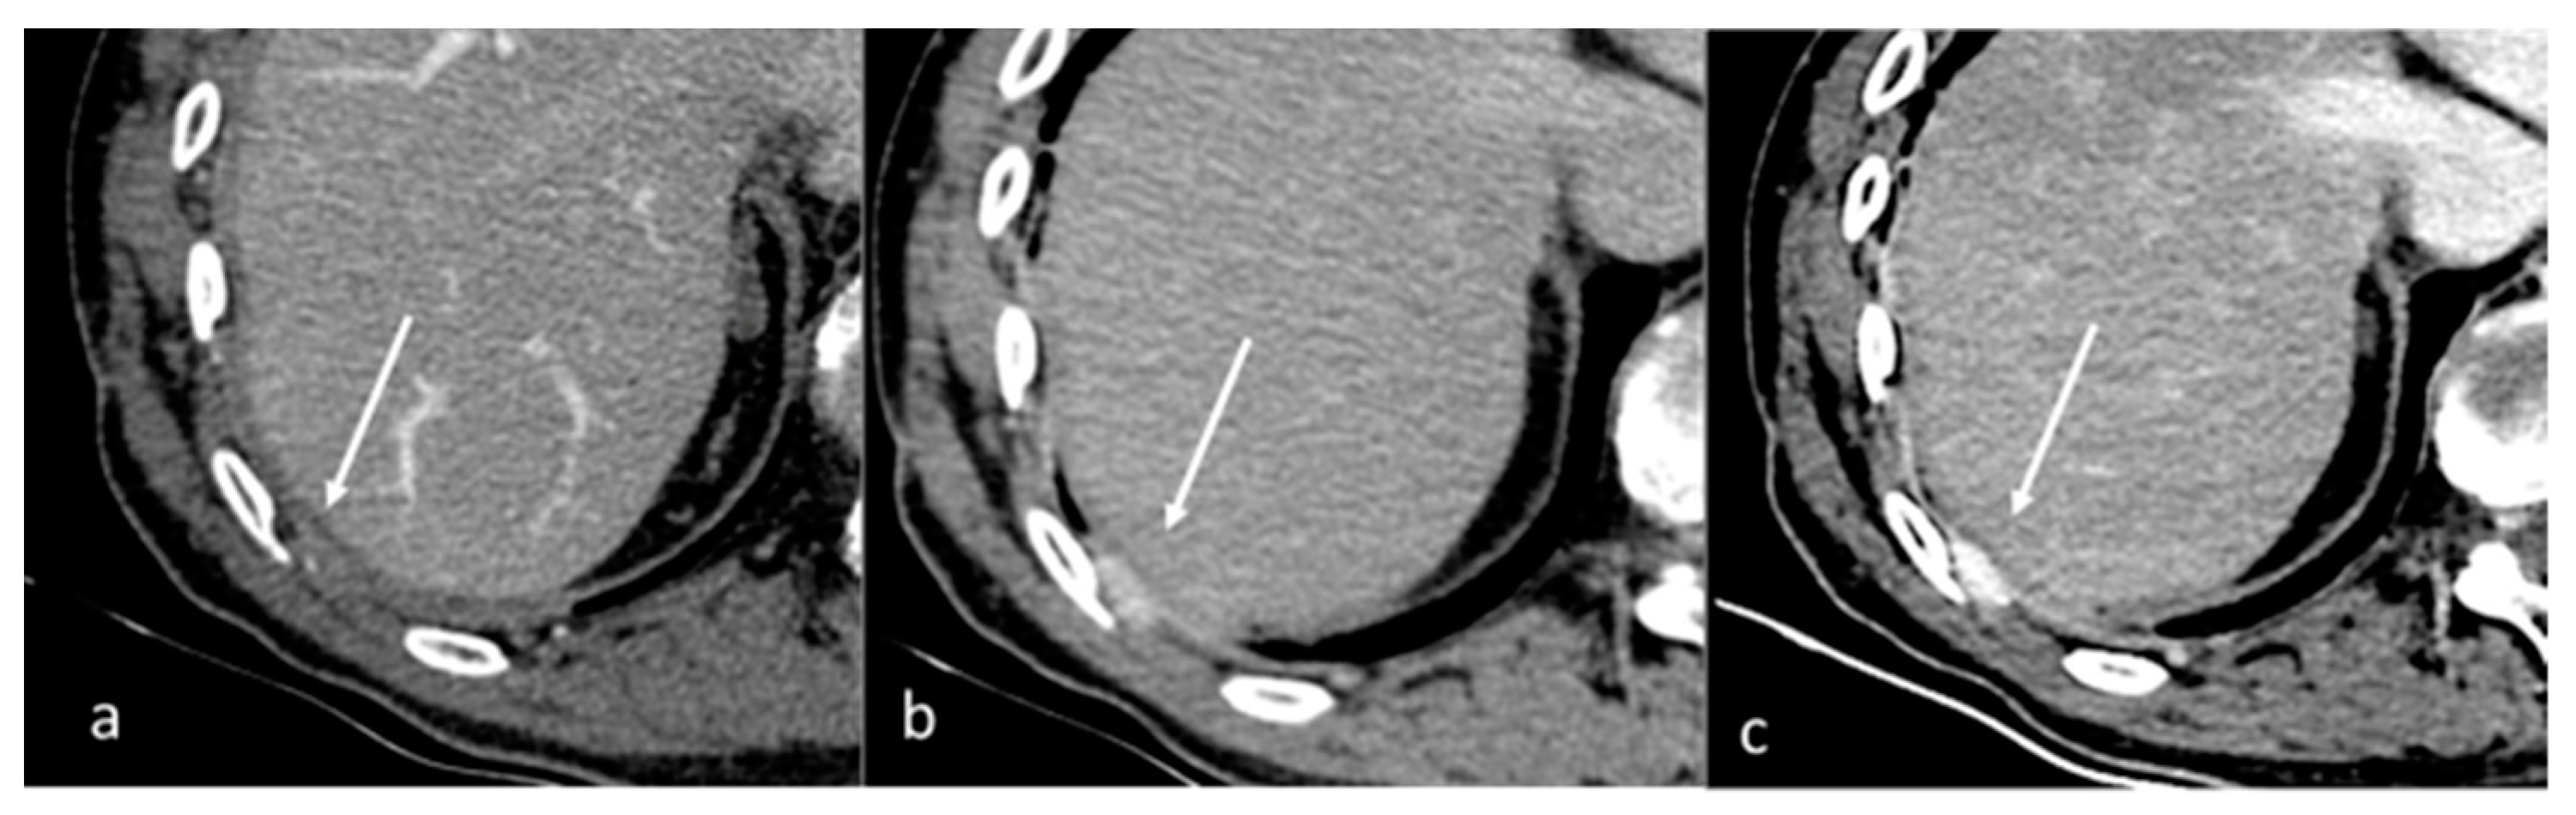

| Kosmala et al. [73] Prospective study | Germany | To determine the diagnostic performance of DECT for the detection of bone marrow infiltration in patients with multiple myeloma by using a VNCa technique | 34 | Somatom Force, Siemens Healthineers,, Germany. No C.I. related to this article | Visual and ROI-based analyses of dual-energy VNCa images had excellent diagnostic performance for assessing bone marrow infiltration in patients with multiple myeloma with precision comparable to that of MR imaging. |

| Kosmala et al. [74] Retrospective study | Germany | To evaluate whether different MRI patterns also result in different bone marrow DECT VNCa attenuation values | 53 | Somatom Force; Siemens Healthineers t One author (BK) is an employee of Siemens Healthcare | Bone marrow VNCa attenuation numbers of various imaging patterns in patients with plasma cell disorders differ significantly and a diffuse imaging pattern can be determined confidently using DECT, when ROIs are carefully selected on the basis of MRI findings. |

| Ishiwata et al. [75] Retrospective study | Japan | To examine whether water-hydroxyapatite images improve the diagnostic accuracy of bone metastasis compared with non-contrast CT alone | 83 | Revolution CT, GE Healthcare, Waukesha, USA No C.I. | CT with water-hydroxyapatite images reduces the need for additional radiographic imaging, potentially reducing costs and radiation exposure. |

| Borggrefe et al. [76] Retrospective study | Germany | To evaluate quantitative iodine density mapping as a quantitative biomarker for the separation of vertebral trabecular bone metastases from healthy-appearing trabecular bone | 43 | IQon Spectral Detector CT, Philips Healthcare D.M. and J.B. received honorarium from Philips for scientific lectures | Iodine density measured yielded highest sensitivity and specificity for the statistical differentiation of vertebral trabecular metastases and healthy trabecular bone using an iodine density threshold of 4.5 mg/mL |

| Huang et al. [77] Retrospective study | USA | To evaluate the sensitivity, tumor conspicuity, and image quality of different material decomposition images of phantoms and patients with nearly isodense bone metastases using rapid-kilovoltage-switching DECT. | 6 | Discovery CT750 HD scanner, GE Healthcare B.Y. is a consultant for GE Healthcare | Dual-energy CT with hydroxyapatite–water material decomposition may improve the detection of bone marrow metastases, especially for subtle isodense tumors. |